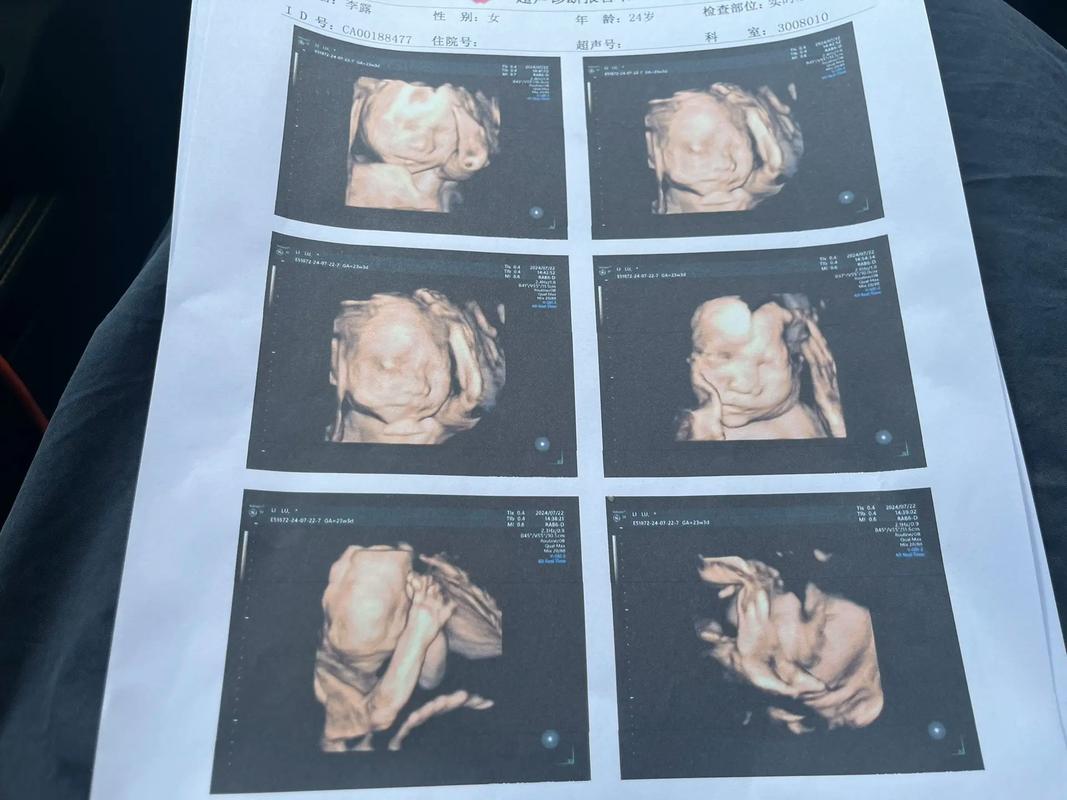

四维彩超,作为孕期的重要检查项目,不仅能帮助医生全面了解胎儿的生长发育情况,还能让准父母提前与宝宝见面。这项技术通过三维图像的实时播放,让准妈妈们仿佛置身于宝宝的“出生现场”,感受那份即将到来的幸福。